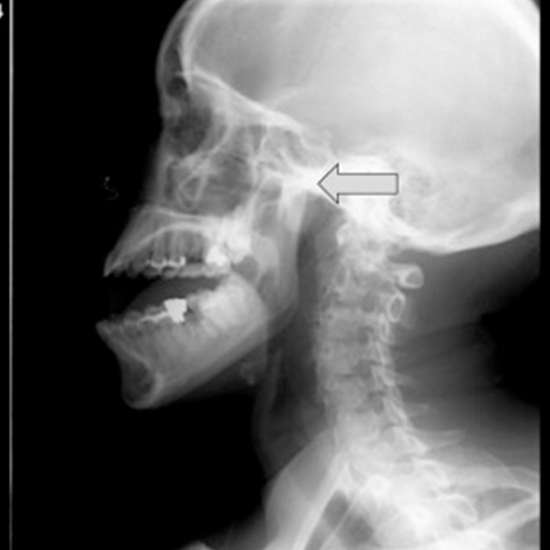

What is an X-ray TMJ (LAT View) Test?

An x-ray of the TMJ area is taken to arrive at a precise diagnosis of the difficulties associated with the pain or trauma. This is done to ensure that the patient receives the best possible treatment. Regarding the LAT (lateral) viewpoint, the X-ray beam is aimed in a lateral direction towards the patient's body.

TMJ problem symptoms include facial, jaw, or ear discomfort, headaches, earaches, pain and pressure behind the eyes, a clicking or popping sound while opening or shutting the mouth, jaw muscle tightness, and facial puffiness. X-rays are used in such cases to diagnose illness.